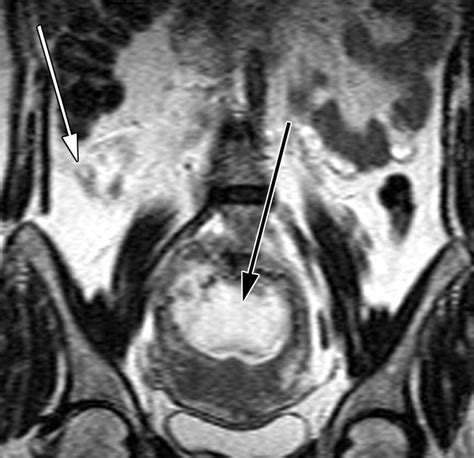

• CT scan: In some cases, a CT scan may be recommended, but it is generally avoided due to radiation exposure. Magnetic resonance imaging (MRI) is a safer alternative.

Early diagnosis is crucial to prevent complications such as appendiceal rupture, which can lead to sepsis and other serious health issues.